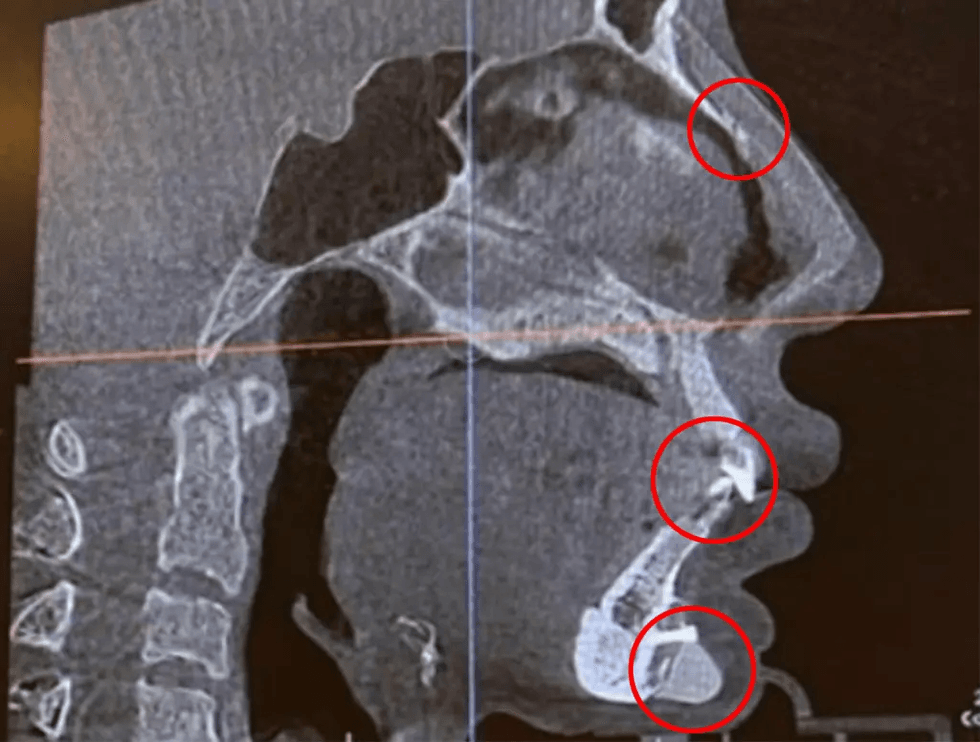

Fang Qiyuan, 36 vjeçe, e njohur ndryshe si Sprite, detajoi zbulimin e saj për më shumë se 1.3 milion ndjekësit e saj në një postim në Instagram. "Proteza e mjekrës që kam pasur tetë vjet më parë la një gozhdë që ishte pothuajse 3 centimetra e gjatë", tha Fang Qiyuan, 36 vjeçe, shkruan The New York Post.

Duke provuar të kalojë përmes një skaneri të sigurisë në aeroport, makina zbuloi një vijë kirurgjikale prej 1 inçi pak më poshtë buzës së poshtme, siç shihet në fotot e saj në Instagram.

Fang beson se goxha ishte lënë atje gjatë një "proteze mjekre" që kishte marrë tetë vjet më parë. Fatkeqësisht, ajo nuk ishte gozhda e vetme kirurgjikale që doli në skanimin me tomografi të kompjuterizuar (CT). "Papritmas zbulova se kam edhe gozhdë në hundën time", zbuloi modelja.

Fotot shoqëruese tregojnë një nga gozhdat pak më lart se buzët e saj të drejtuara poshtë dhe një tjetër në hundën e saj. Me gjithë pamjen si një pushkush me gjilpëra, vidanjat kirurgjikale në përgjithësi nuk janë të dëmshme për pacientin dhe prandaj nuk kërkohet të hiqen.